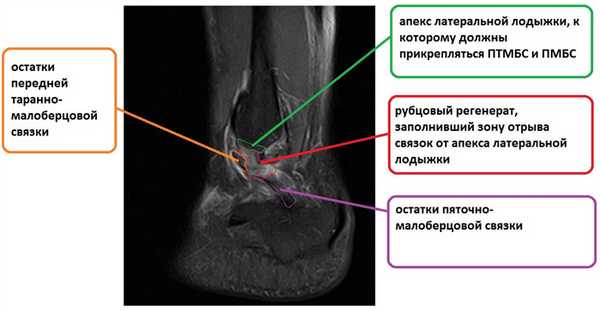

Ниже представлены срезы МРТ в которых наглядно показано расположение повреждённых связочных структур.

На этом этапе пациентка лечилась по стандартному сценарию «растяжение голеностопа». Носила ортез, мазала голеностоп вольтареном и лиотоном, разгружала его при помощи трости. Но в связи с длительно сохраняющимся болевым синдромом было выполнено МРТ, при котором диагностирован застарелый разрыв передней таранно-малоберцовой связки, пяточно-малоберцовой связки правого голеностопного сустава, контузионное повреждение латеральных отделов таранной кости.

Для подтверждения механической нестабильности выполнены стресс-рентгенограммы голеностопного сустава с «варус-стресс тестом» и «тестом переднего выдвижного ящика». Критериями для постановки диагноза нестабильности является ангуляция таранной кости в коронарной плоскости более 4 градусов и смещение таранной кости кпереди в сагиттальной плоскости на 4 мм, или разница с контрлатеральной стороной в 2 градуса и 2 мм соответственно.